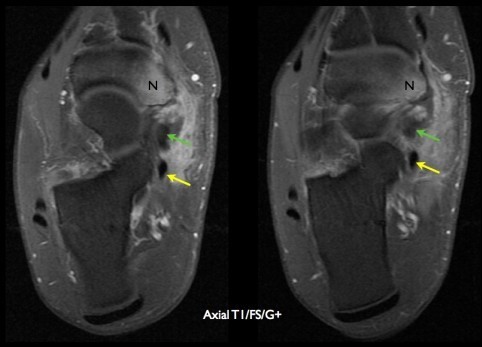

△ 후경골근건(초록색 화살표)의 거대화와 주상골(N)의 골수종

△ 정상적인 장지굴근건(노란색 화살표)과 장모지굴근건(분홍색 화살표)